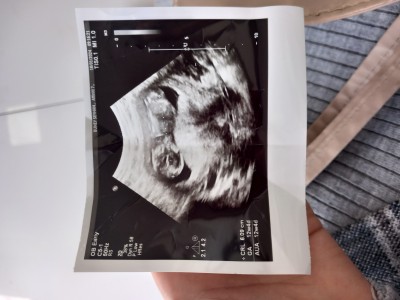

Kızlar ense kalınlığı ölçülmesi mu

Gebelik haftası 12 4

İkili test kan testi ile yapılır başka doktora gidin tekrar crl niz ölçülmus  sadece

Ense kalınlığında bakılıyor y bakmamış mi cnm  evet pazartesi gidecegim

Onu ordan öğrenemeyiz ultrason cihazında kendisi ölçüyor biz anlayamayız ense kalınlığını nazal kemiğin gelişiminee bakıyor down sendromunda geç gelişirmiş nazal kemik doktor özellikle bakmıştı sonra ikili testi bizşm hastanede yapmıyorlardı tüple araştırma hastanesinr gitti kanım  ordan 2 hsfta sonra sonucum geldi doktora gösterdim iyi güzel bebeğin sağlıklı dedi

Burda gözükmüyor. İkili en geç 13+6 ya kadar yapılıyor 14+0 oIursanız yapılmaz. Geç kalmadan başka bi doktorda yaptırın.

İkili taramanın ultrasonu farklı oluyor onu doktor odasındaki ultrasonla yapmıyor büyük usg ye gönderiyor sonrada kan vermeye gidiyorsun ense kalınlığıni ayrı bir doktor bakıyor canm